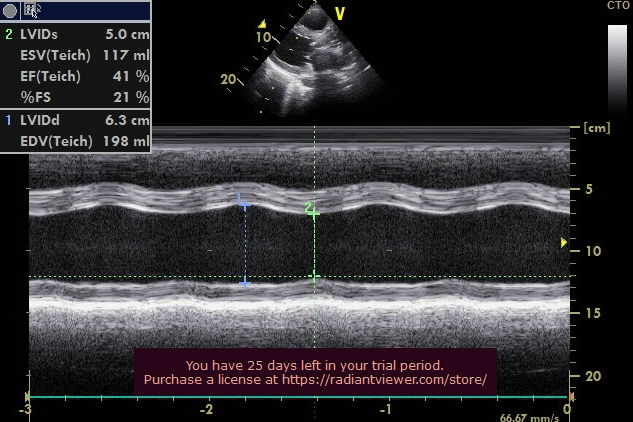

患者:老年男性,因发作性胸闷咳嗽2年,加重伴晕厥10余天收治入院,超声心动图显示主动脉瓣重度钙化增厚,回声增强,开放受限。平均跨瓣压差 48mmHg,最大压差84mmHg,瓣上速度 4.77m/s,EF32%,提示主动脉瓣重度狭窄并伴有轻度关闭不全。

术后即刻压差7mmHg,流速1.3m/s,EF41%。